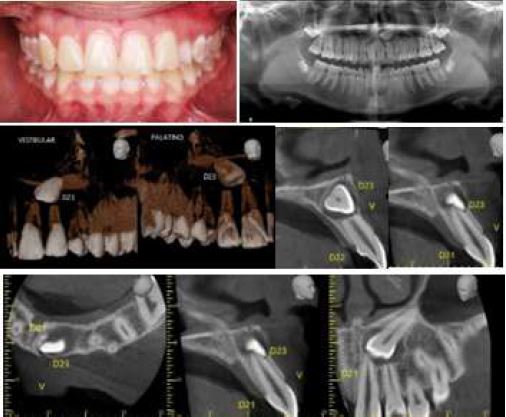

Clinical and Radiographic Follow-up

An analysis of the control periapical radiographs showed a marked improvement in the path of eruption of both canines (Figure 10); therefore, teeth 53 and 63 were extracted and the patient was scheduled for surgery to change the traction vector of 23. Surgery was performed on the vestibular gingiva of 23, the button was relocated and a new chain was placed which was passed through the alveolus of 63. The flap was repositioned and sutured. A 0.017" x 0.025" TMA cantilever was installed on band auxiliary tube on 26. Both cantilevers were fitted with a distoclusal traction vector. In addition, open springs were placed between 14 and 12 and between 22 and 25 to expand the space and facilitate the accommodation of the canines (Figure 10).

Follow-Up Images, Caso 2

FIGURE 10

The radiographic image shows the new position of teeth 13 and 23. The repositioning of the direct cementation buttons and the new traction vector are also evident. Activation of the second-generation bilateral chains attached to the steel arm welded to the cemented bands on teeth 26 and 16 is also shown. Source: the authors with permission from the patient.

When reaching the most occlusal height, adhesion of 13 was performed and ligated at a distance with an elastic thread up to the arch. In 23, a palatal adhesion button was adhered and a chain installed to generate a coupler and derotate it (Figure 11). Once the rotation was resolved, a bracket was attached to 23 and continued to align until fully incorporated into the continuous arch. Likewise, the alignment of 13 and the lower teeth was completed (Figure 12).

Final Alignment Image of 13 and 23, Case 2

FIGURE 11

Source: the authors with permission from the patient.

Final Records, Case 2

FIGURE 12